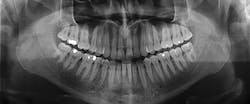

Los Algodones is a busy place and I myself can attest to the prices. A teeth cleaning is $15 to $20 and the average crown is around $250—four times less than a dentist's office in the US and even cheaper than having insurance! You might think that in Mexico, service would be poor and equipment would be outdated. But quite the contrary; Los Algodones has all the modern equipment of US dental offices, and even more photonics-related equipment in some cases.

Zoom Laser Whitening using an ultraviolet laser and special hydrogen peroxide gel (see figure below from Doctor Iniguez) is available from numerous Los Algodones dentists. Incredibly, the treatment is a one-time affair that takes 45 minutes versus multiple chemical treatments for non-laser-based whitening.Sani also has the latest laser equipment (http://sanidentalgroup.com/treatments-description.html#laser) to treat periodontal diseases, stimulate tissue regeneration, and for cleaning and whitening procedures. Doctors Figueroa and Perez (http://www.losalgodones.com/dr_figueroa_perez.htm) offer an FDA-approved Periodontal Dental Laser for laser gum treatment, and while I couldn't find anything in a web search on the use of 3D laser-printed implants being fabricated in Los Algodones, my guess is that in order to create implants much faster and cheaper than in the US, laser-based 3D printers must exist somewhere in the town. Perhaps I need to embark on a field trip donning my Laser Focus World editorial credentials to see what I can find out?